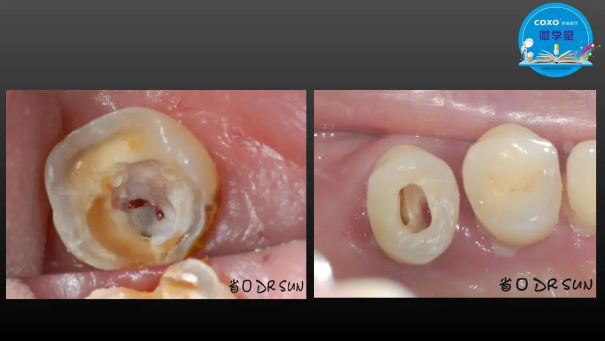

主任醫(yī)師,牙體牙髓副主任, 廣東省口腔醫(yī)院牙體牙髓科 主任醫(yī)師。2003年碩士研究生畢業(yè),研究方向為牙體牙髓病學,擅長于牙體牙髓病的診斷、齲齒、牙髓炎、根尖周病的治療以及前牙美容修復。